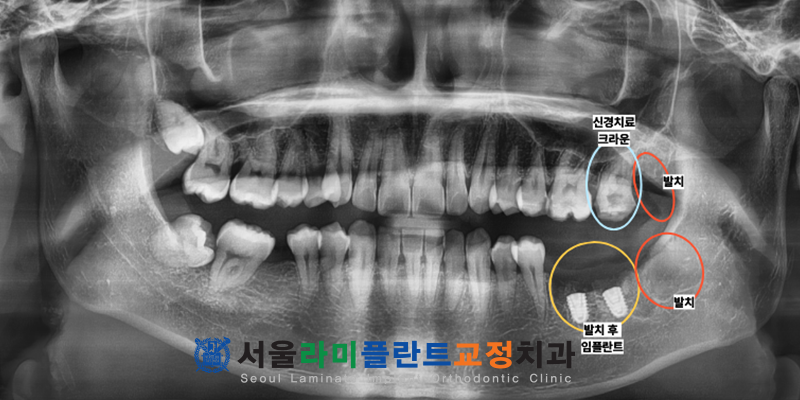

환자분의 구강 상태를 정밀하게 진단한 결과

다수의 어금니가 심각한 우식으로 인해

기능을 완전히 상실하여

발치가 불가피한 상태였는데요.

또한 잇몸 속에 파묻힌 매복 사랑니 또한

주변 치아에 악영향을 주고 있어

발치가 시급한 상황이었습니다.

첫 번째 수면 진료에서는

왼쪽 부위의 문제를 치료하기 위해

기능을 잃은 어금니를 발치하고

임플란트를 식립하였으며

매복사랑니 발치도 함께 이루어졌습니다.

더불어 살릴 수 있는 치아에 대해서는

정밀한 신경치료를 병행하여

자연 치아를 보존하기 위한

조치를 취하였는데요.